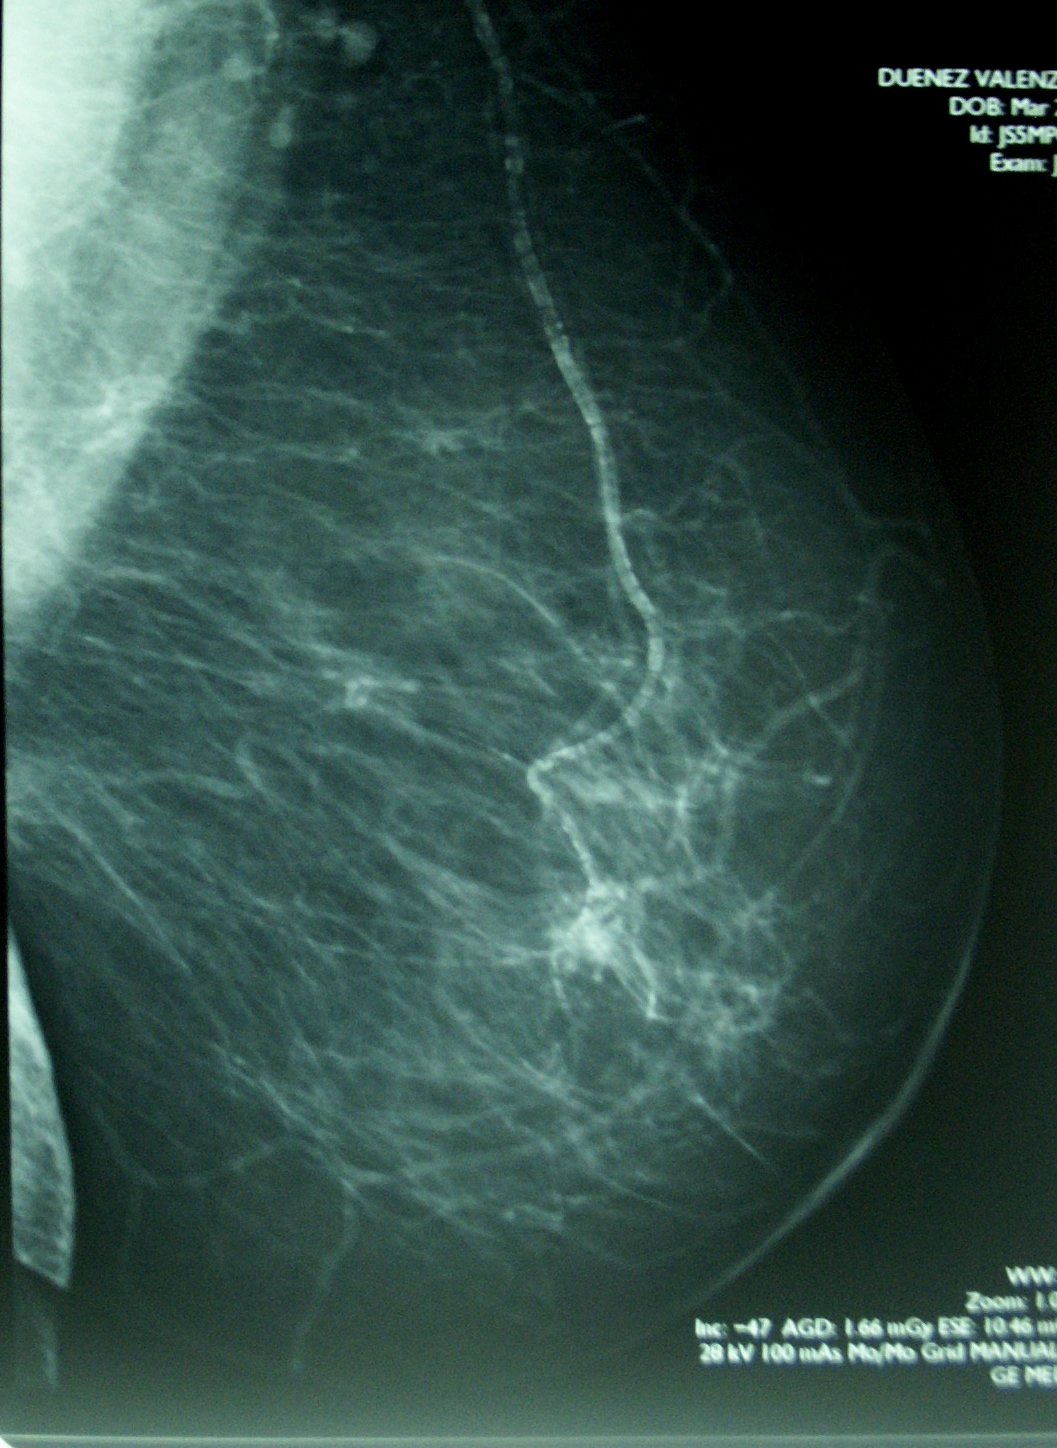

Un buon esame deve essere efficace ai fini della diagnosi precoce ed allo stesso tempo sicuro per il paziente, questo comporta l’utilizzo di apparecchi in grado di rilevare anche le più piccole lesioni, mantenendo al contempo l’esposizione ai raggi-X quanto più ridotta possibile.